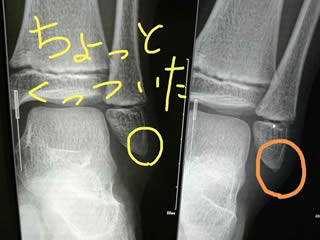

1週間後、ちょっとくっついてきた模様。